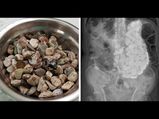

ಕಲ್ಲು, ಮುಚ್ಚಳ, ನಾಣ್ಯ ನುಂಗಿ ತನ್ನ ಆತಂಕ ನಿವಾರಿಸಿಕೊಳ್ಳುತಿದ್ದ ವ್ಯಕ್ತಿ!